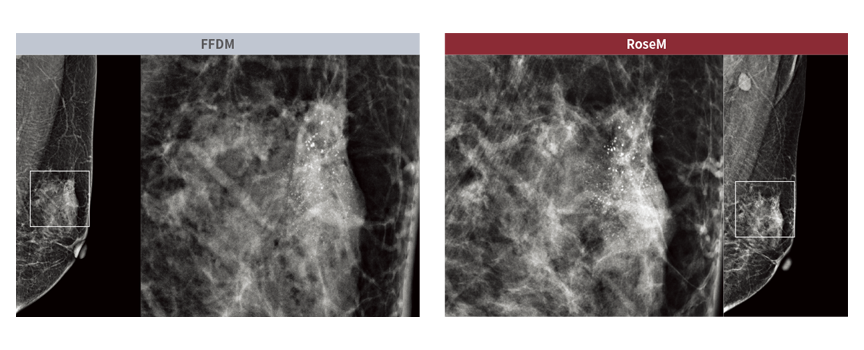

Jakość obrazu uzyskiwana dzięki systemom linii Rose M otrzymała najwyższe noty. Lekarze na całym świecie ocenili ją jako porównywalną do systemów FFDM najwyższej klasy!

Wpływa na to także optymalna dobrana wielkość pixela, która wynosi 76 µm.

Porównanie jakości obrazu: RoseM vs FFDM